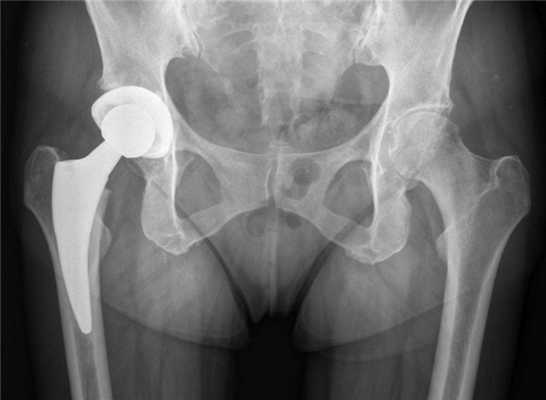

(Слева) Рентгенография в ПЗ проекции: подвижная тотальная артропластика голеностопного сустава, наиболее часто применяемый в США двухкомпонентный протез. Визуализируется синдесмозный артродез, увеличивающий площадь костной поверхности для большеберцового компонента, который снижает возможность развития нестабильности или смещения. Компонент таранной кости расположен с наружной ротацией 20°. Минимальное просветление, визуализируемое на поверхности соприкосновения кости с цементом, не является признаком расшатывания.

(Справа) Рентгенография в боковой проекции, этот же случай: осложнения в виде образования мягких тканей позади протеза и лизис большеберцовой и таранной костей.

(Справа) Рентгенография в боковой проекции, этот же случай: осложнения в виде образования мягких тканей позади протеза и лизис большеберцовой и таранной костей. (Слева) КТ кости, сагиттальный срез, этот же случай: отмечается большая чувствительность КТ по сравнению с рентгенографией при визуализации распространенности литических очагов. Обратите внимание, что полиэтиленовый компонент выглядит симметричным, нет признаков его износа.